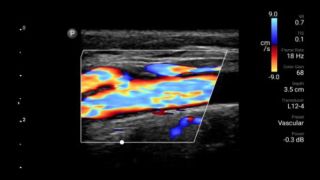

Reduzca las complicaciones en procedimientos guiados por aguja

El ultrasonido portátil Lumify para anestesiología le ayuda a visualizar claramente la definición de los bordes con la colocación de la aguja, los nervios circundantes, los vasos sanguíneos y los planos fasciales.

Transductor de matriz lineal de banda ancha Lumify L12-4